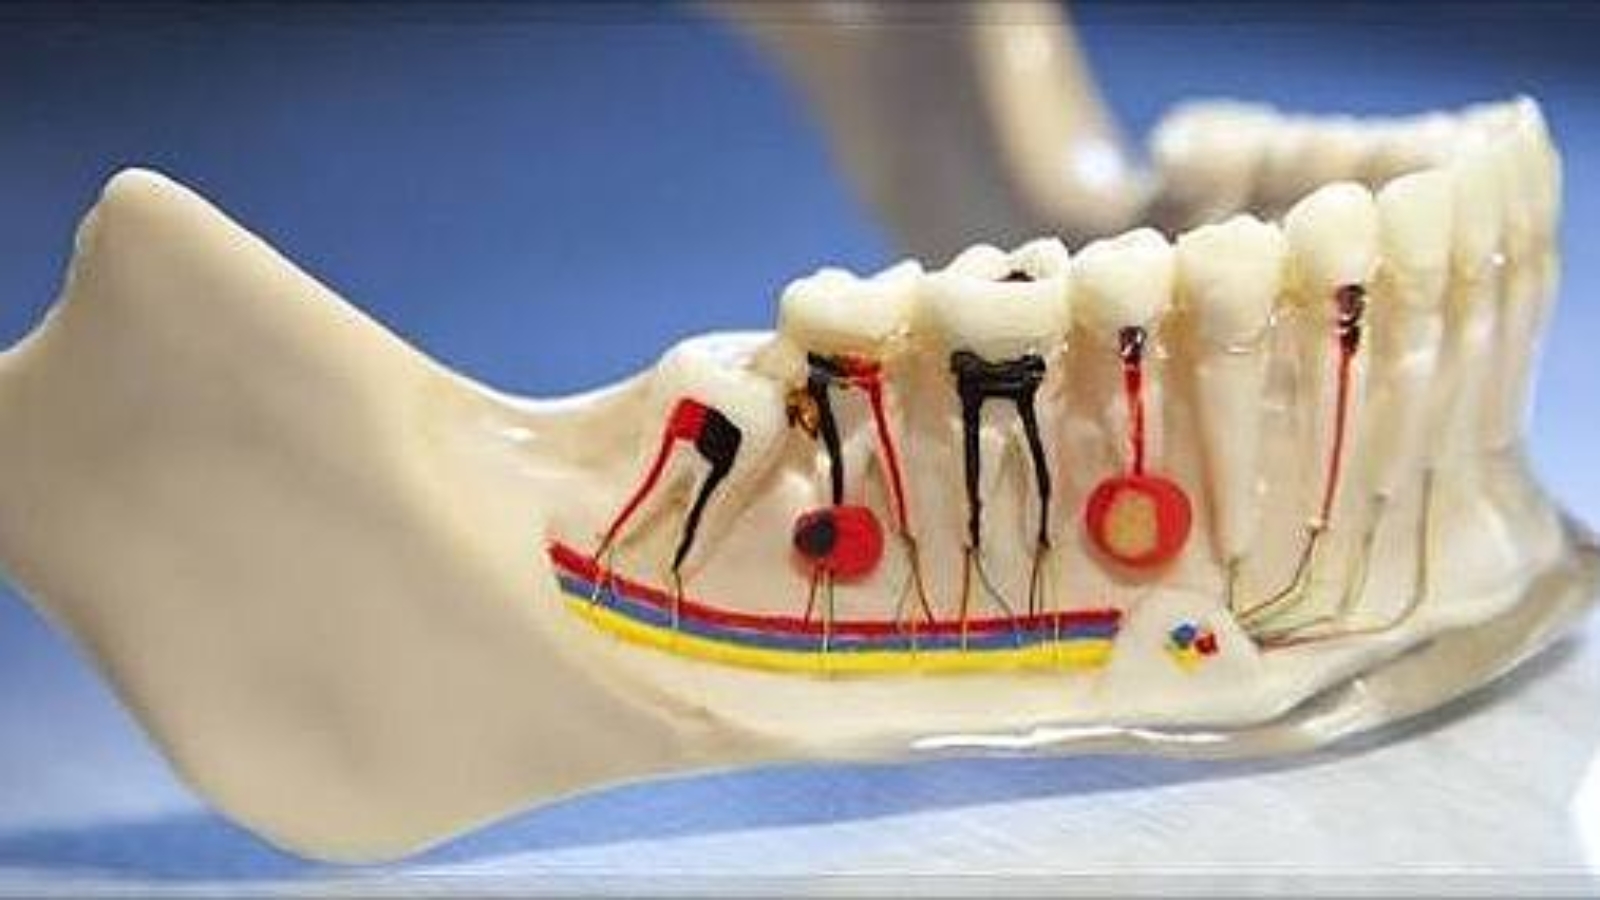

The essence of hemisection lies in removing the affected root together with the corresponding portion of the crown while preserving the intact root. This approach allows retention of the patient’s own dental tissues, maintenance of alveolar bone volume, and avoidance of immediate prosthetic replacement or implant placement. At DentalClinic24, the decision to perform hemisection is made only after comprehensive diagnostics and assessment of functional load.

The primary indication for hemisection is localised root damage – such as a vertical root fracture, advanced periodontal destruction, resorptive defects, or endodontic complications confined to one root. At the same time, the preserved root must demonstrate sufficient structural integrity and a favourable prognosis. At DentalClinic24, this assessment includes analysis of bone support, root anatomy, and the condition of the pulp-dentin complex.

Biomechanics plays a central role in determining treatment success. Following hemisection, occlusal load distribution changes, and the remaining root must function under new mechanical conditions. At DentalClinic24, anticipated load vectors are evaluated in advance to prevent overload of the preserved root and to ensure long-term functional stability.

The technical complexity of hemisection requires a high level of clinical precision. Errors during root separation or removal of the affected segment may compromise the prognosis of the preserved portion. For this reason, at DentalClinic24 hemisection is performed only when strict diagnostic criteria are met and atraumatic surgical execution can be ensured.